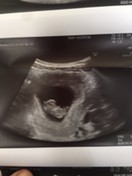

ขอดูตัวน้อยของแม่ไปทีมมกราคมหน่อยจ้า☺️☺️ อาการแม่ๆเป็นยังไงกันบ้างคะ บ้านนี้กินไม่ได้เลยกินนมก็ไม่ได้ออกทางเดิมตลอด🥺 #ทีมมกราคม 19 มกราคม 2566